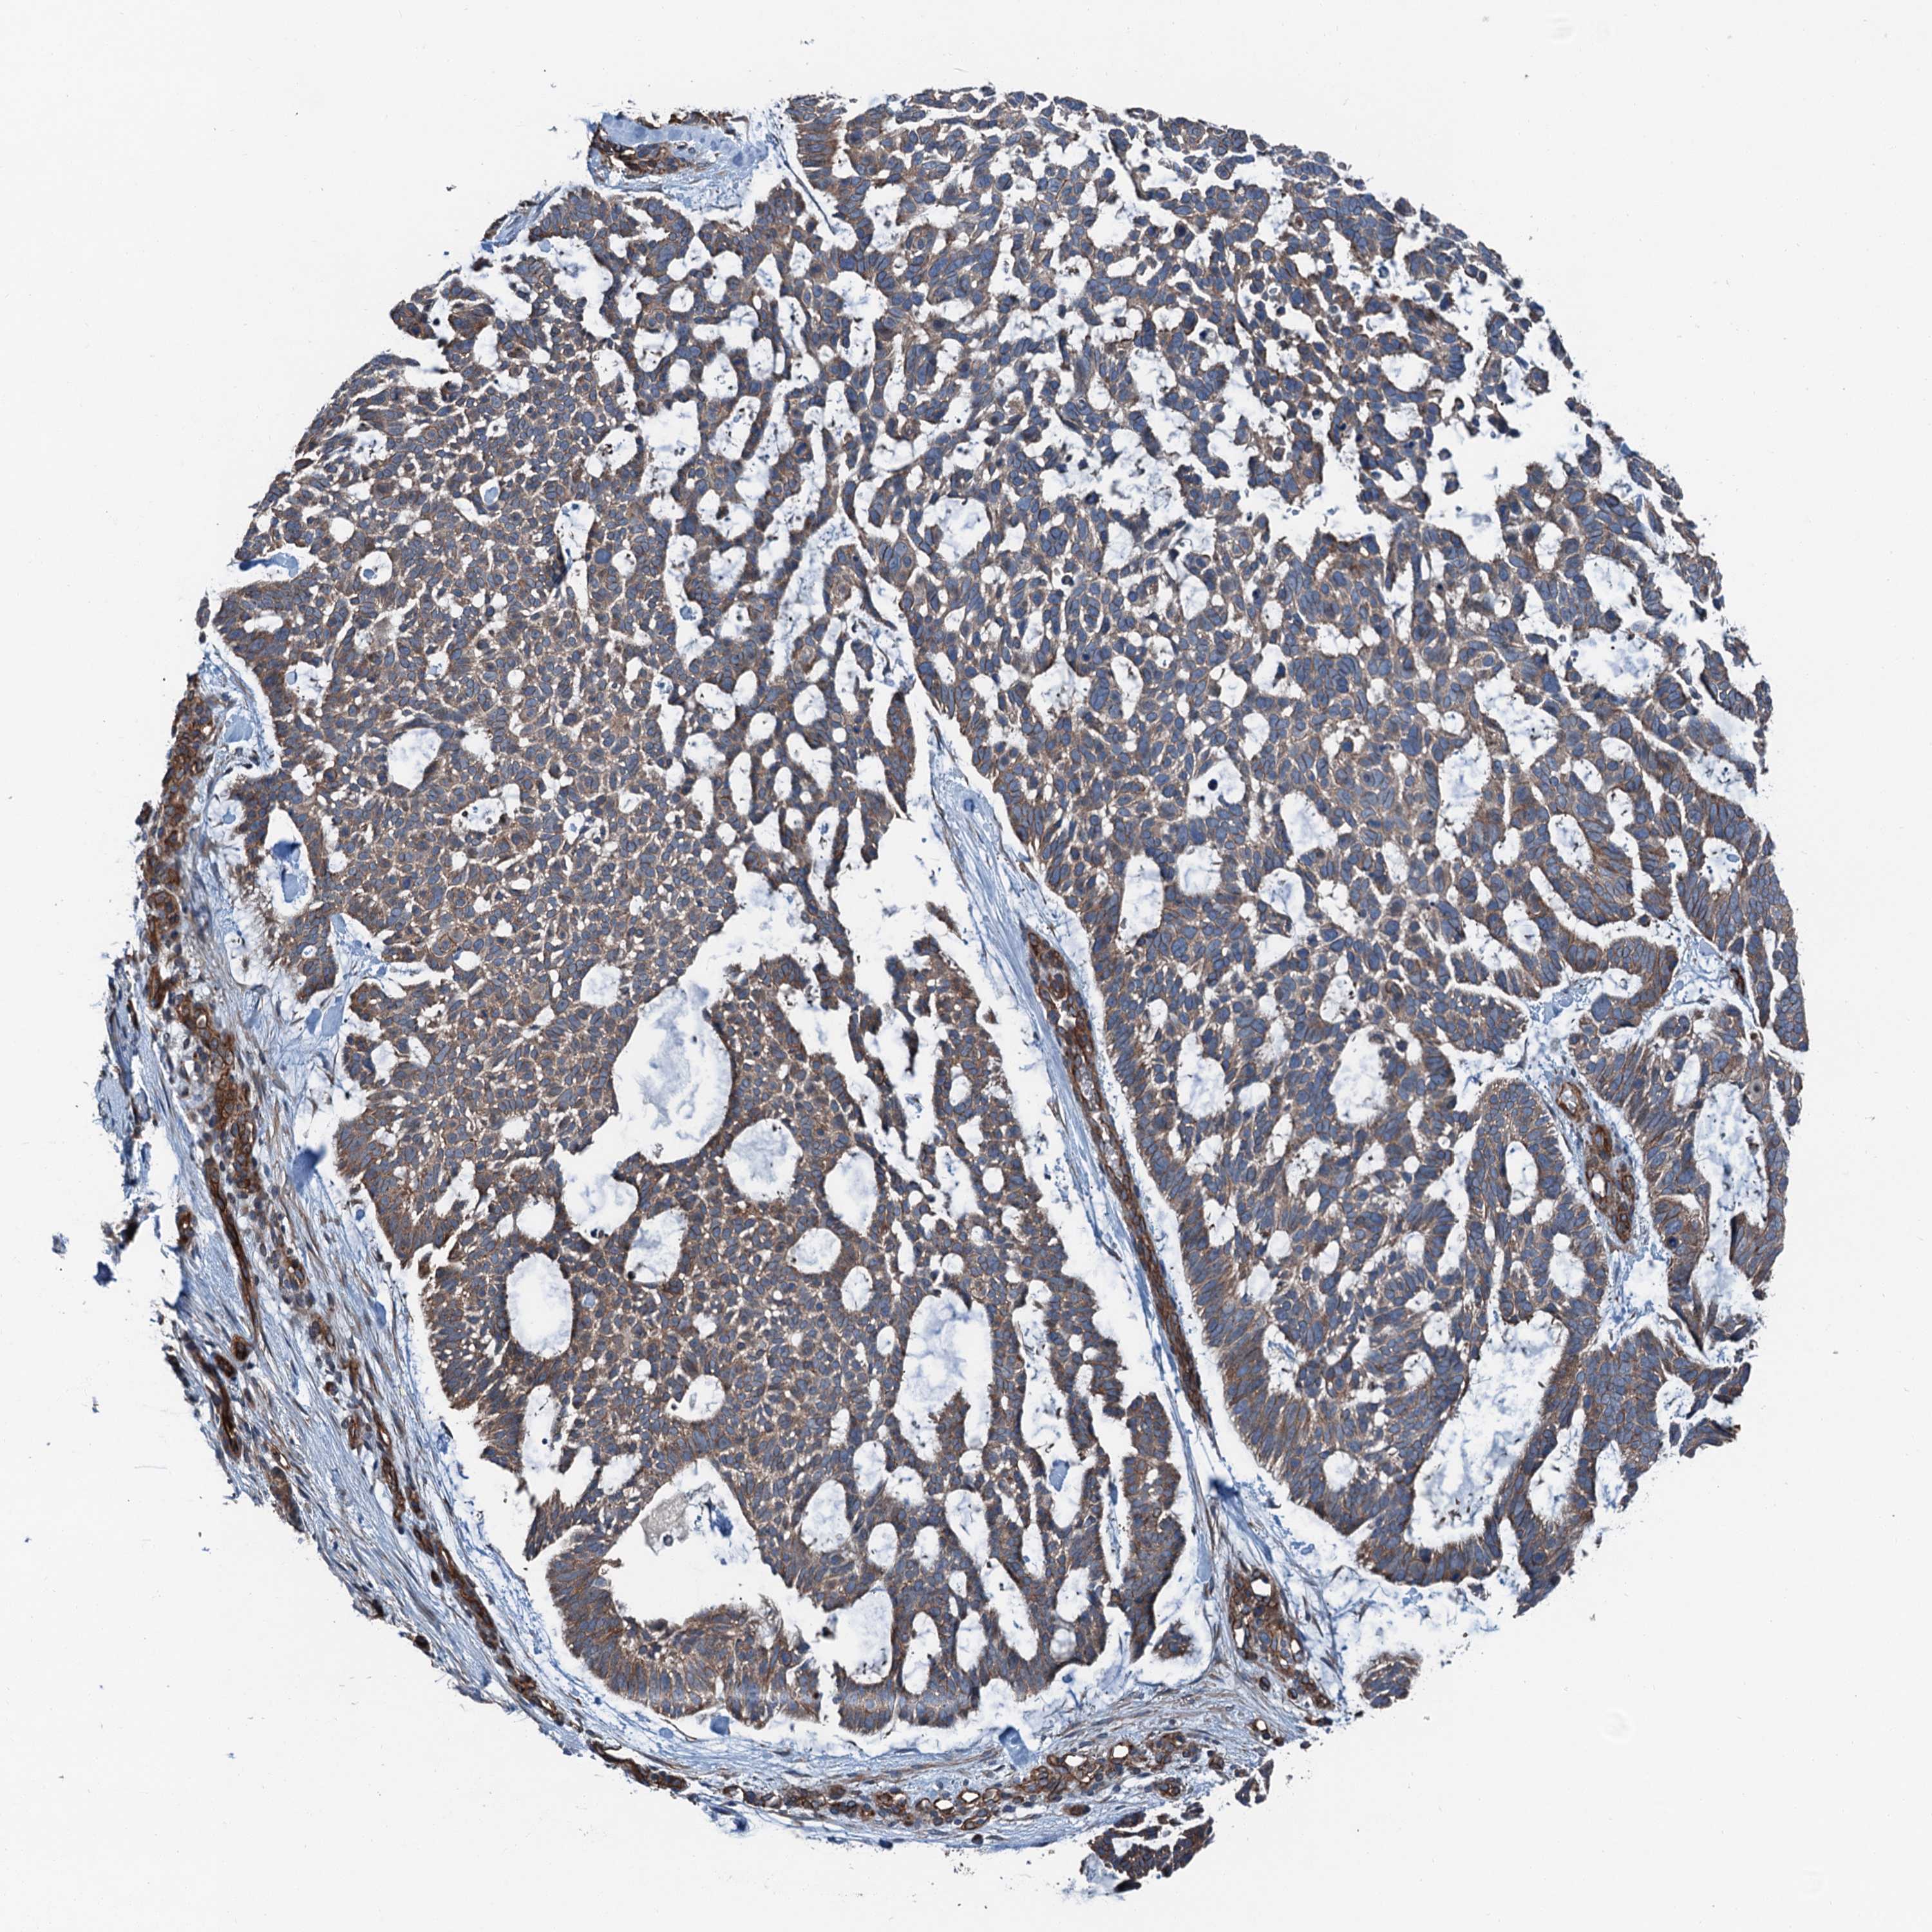

SKIN CANCER - Protein expressioni

A mouse-over function shows sample information and annotation data. Click on an image to view it in a full screen mode. Samples can be filtered based on level of antibody staining by selecting one or several of the following categories: high, medium, low and not detected. The assay and annotation is described here.

Antibody stainingi

Antibody staining in the annotated cell types in the current human tissue is reported as not detected, low, medium, or high, based on conventional immunohistochemistry profiling in selected tissues. This score is based on the combination of the staining intensity and fraction of stained cells.

Each image is clickable and will lead to virtual microscopy that enables deeper exploration of all samples and also displays staining intensity scores, fraction scores and subcellular localization as well as patient and tissue information for each sample.

Antibody HPA041353

Staining

High

Medium

Low

Not detected

Intensity

Strong

Moderate

Weak

Negative

Quantity

>75%

75%-25%

<25%

None

Location

Nuclear

Cytoplasmic/membranous

Cytoplasmic/membranous,nuclear

Squamous cell carcinoma, NOS